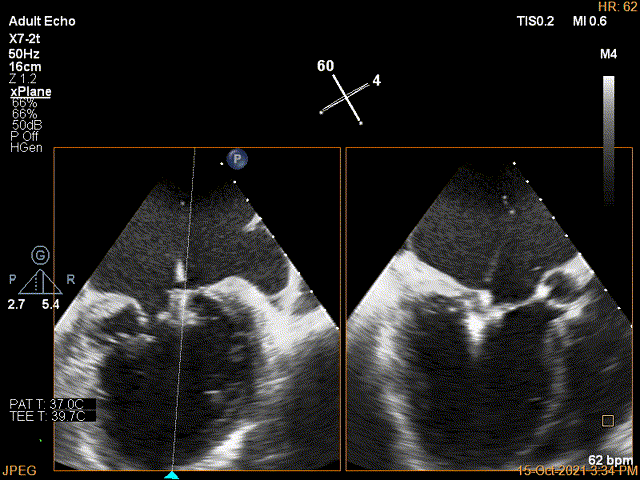

术前超声评估结果

术前超声诊断

3D-color MV view:极大量返流,1、2区均有受累

Qlab软件勾画估测瓣口面积约:6.23cm²